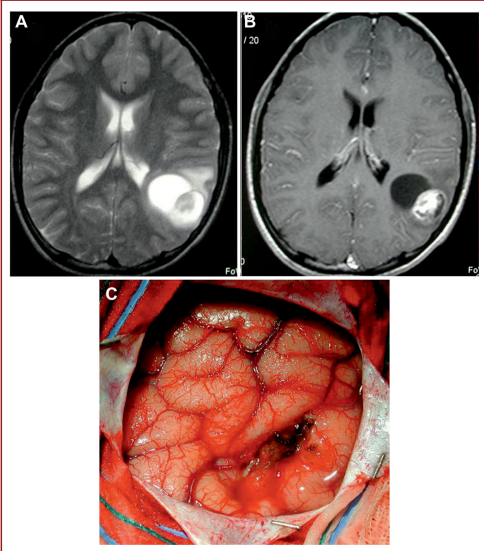

该论文通过回顾性分析近15年来在同一机构手术治疗的143例儿童幕上病变,将其分为A组-68例以大脑半球肿瘤为主要治疗手段的儿童,和B组-75例儿童经皮外途径治疗,主要治疗鞍上和视神经肿瘤。排除可能有“癫痫”倾向的患者,如术前癫痫发作。

平均随访6.8年,A组和B组PSs发生率(11.7%vs14.5%)和PE(4.5%vs6.5%),发作时间和类型无明显差异。A组皮质切开术的大小(<3平方厘米 vs>3平方厘米)对癫痫的发生没有影响,并且两组考虑的其他变量(年龄、性别、病变切除程度)。

癫痫发作在头部受伤或神经外科手术后立即(24小时内)、早期(1周内)或晚期(1周以上)。神经外科患者经常经历的是立即和早期癫痫发作。然而,只有迟发性癫痫才被认为是“的”癫痫,因为有癫痫病灶的危险组织形成。这个PSs的发病率成人为10%-20%,儿童为5%-15%,PE的估计频率为5%-7%,较早期和孤立性癫痫的少报、术前癫痫的存在或术前电解失衡,以及AED预防措施的使用,使得评估PSs的真实频率变得困难。本研究证实了儿童术后癫痫发作的发生率(PSs:13.2%;PE:5.6%),没有上述限制的偏差。据其他作者观察,癫痫一般在术后78.5天开始发作(1年后无一例),主要表现为局灶性或“无意识”全身性发作。

本研究显示手术皮质“外伤”不代表儿童术后癫痫发作和PE的危险因素。根据目前的分析和文献,似乎还涉及其他原因(即电解失衡和脑胶质增生)。这些信息对于术前手术计划和术后管理重要。成人和前瞻性研究都需要验证。